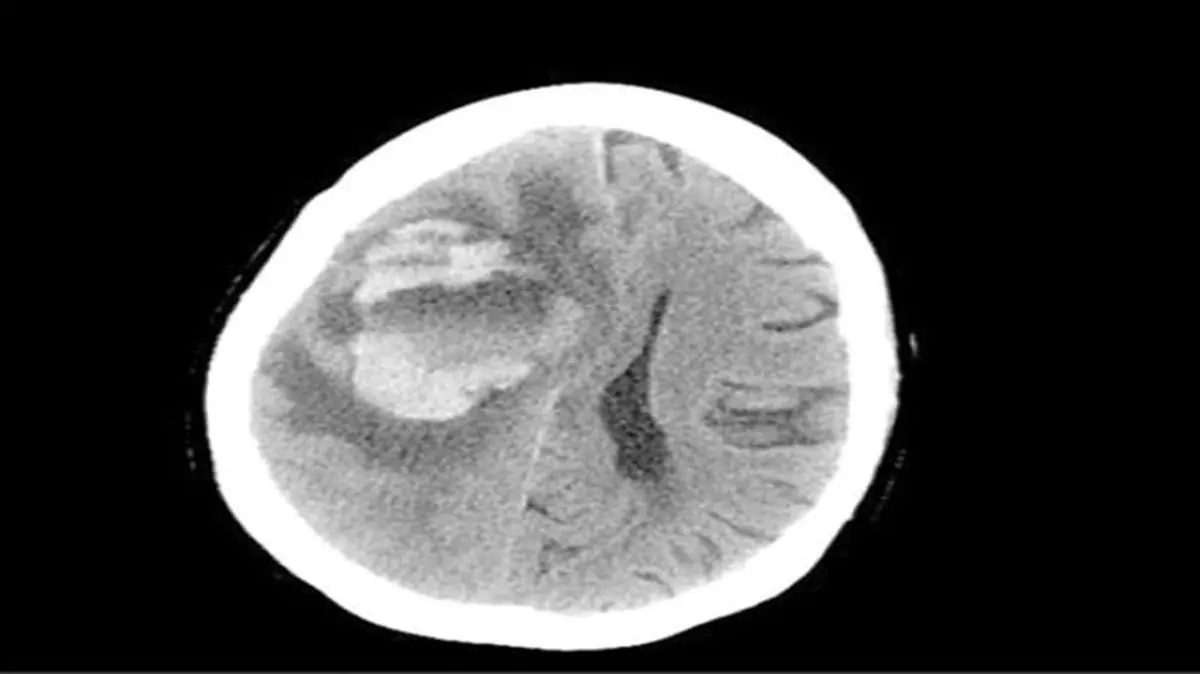

حوادث رکنا: زنی 69ساله چندی پس از شستوشوی سینوسهایش با آب لولهکشی به بیمارستان مراجعه کرده و در آنجا جان باخت.

پزشکان بیمارستانی در آمریکا پس از کالبدشکافی متوجه شدند گونهای از یک آمیب (جاندار تکیاختهای) نادر از طریق آب وارد مغز او شده و بخشی از آنرا خورده است. پزشکان در مصاحبه با سایت دیلیمیل، استفاده از آب لولهکشی بهجای محلول شستوشوی سینوس را عامل این مرگ اعلام کردند.اخبار 24 ساعت گذشته رکنا را از دست ندهید